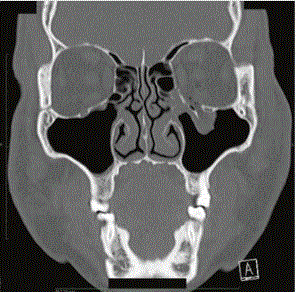

Welchen wichtig Knochen siehst du hier

Das Os Ethmoidale =Siebbeinknochen

• ein Knochen den wir von außen betrachtet nur leicht an der medialen Orbitawand sehen, doch sehr wichtig ist und nach innen eine viel größere Ausdehnung hat, als gedacht!

Das Os ethmoidale ist an der Bildung der Schädelhöhle, der Nasenhöhle und der Orbita beteiligt. Der Knochen lässt sich in 4 Abschnitte gliedern: die Lamina cribrosa, die Lamina perpendicularis und das paarige Labyrinth (Labyrinthus ethmoidalis).